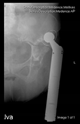

The direction of the cup stem was determined by the guide wire. The aiming device was needed to introduce this wire. After removing the aiming device, the next step was the drilling. Since a cannulated drill bit was used, the previously installed wire could guide the process. A self-positioning reaming tool was then used in the drilled channel. In the prepared cavity, the cup was fitted perfectly. Of the two stemmed cups available to us, the McMinn cup (Waldemar Link, Hamburg, Germany) had the simpler geometry and was therefore chosen. The stemmed cup was inserted according to the manufacturer’s recommendation. In the presence of a significant bone defect, a synthetic bone graft may be impacted for substitution.

The radiological examination allowed us to verify the close bone-to-implant contact and the unchanged position of the implant during follow-up.

In all the cases operated with the above-described targeting procedure, the stems of the cups remained between the cortical bone surfaces without perforation of the linea terminalis, as shown by postoperative radiographs. There were no complicated surgical situations. In 16 cases, the wound healings were uneventful, and the hips were able to bear weight again after postoperative rehabilitation.